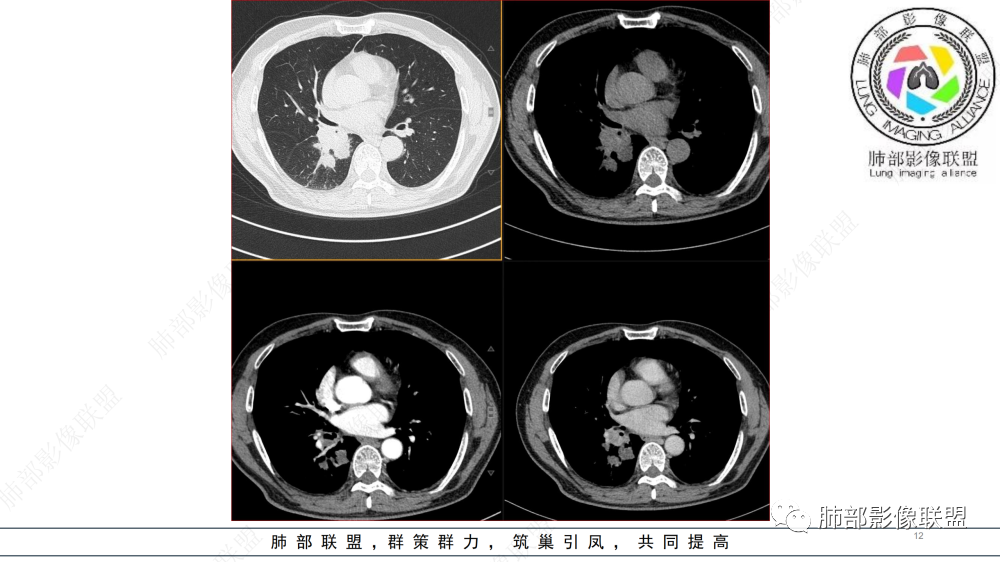

晨读 右肺中间段支气管至下叶支气管部分狭窄及堵塞,管壁偏侧增厚腔内外侵犯,软组织肿块形成,远侧肺内阻塞性炎症。考虑恶性病变,鳞癌,类癌可能

中年男性,咳嗽咳痰半年,有痰中带血,肿瘤标志物角蛋白稍高,右肺下叶支气管腔内肿块,支气管截断,有强化,考虑肺癌,鳞癌可能,鉴别类癌,粘液表皮癌等。

晨读:男,57岁,咳嗽咳痰半年,右肺下叶支气管腔内肿块影,管壁增厚,管腔狭窄,增强扫描呈不均匀性强化,考虑恶性病变,鳞癌可能。

右肺下叶肺门区肿块,向中间段支气管突出,下叶支气管阻塞狭窄,腔内外侵犯,不均匀强化,内可见低密度,冠状位病变沿支气管走行生长,远侧肺内阻塞性炎症,考虑鳞癌,鉴别类癌

中老年男性,右肺下叶背段支气管内新生物,近端可见息肉样突起,远端沿分支支气管生长堵塞,肺门口病灶增强后明显强化,峰值达140hu,远端部分强化不明显考虑粘液栓,考虑典型类癌,鉴别鳞癌。

右肺叶中间段支气管见软组织影不完全阻塞及管腔变窄,向管腔外突破,向下叶背段浸润性生长,见指套及息肉样特点,不均匀明显强化,右肺下叶背段少许阻塞性炎症,肯定恶性肿瘤,小细胞Ca首先,支气管疾病谱恶性肿瘤:类癌,鳞癌,囊腺癌,粘液表皮样癌,与鳞癌,囊腺癌鉴别,支气管镜取材活检可以明确诊断。

晨读:男,57,咳嗽半年,痰中带血3天。胸部CT:右中间段支气管到下叶支气管堵塞性狭窄,管腔内见软组织肿块,壁内外侵犯,长轴沿气道延展,下叶基底多段累及,病变纵径大于横径,远侧可见索条、阻塞性炎症。考虑恶性,腺样囊腺癌?鳞?鉴别N内分泌类、炎性肉芽肿等